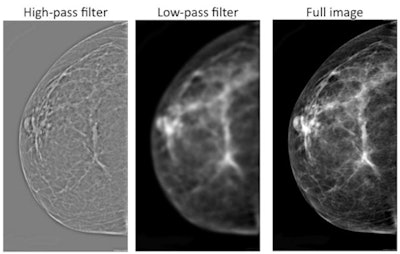

So the group tried applying image-processing filters to the images to see if these made a difference. In one experiment, they used a filter that allowed high frequencies to pass through (high pass), resulting in images in which grayscale levels were similar but fine details were more visible. They also employed a filter that allowed low frequencies to pass through (low pass), which produced fuzzy images with more grayscale variation.

Images demonstrate mammograms with various levels of filtering, from high-pass image at left to unfiltered image at right. Courtesy of PNAS.Interestingly, they found that radiologists viewing either the high-pass images or the unfiltered images performed better than chance in detecting abnormal mammograms, while those viewing low-pass images did not. This led the group to speculate that something in the high-frequency images is contributing to the gist signal that radiologists are picking up on.